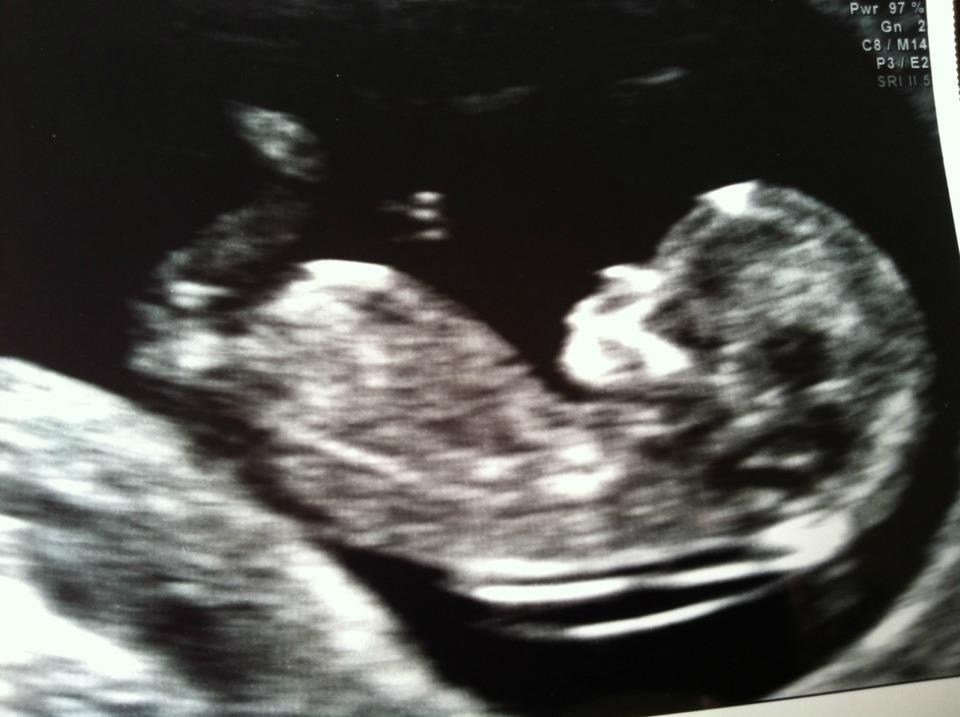

Så har vi her til morgen været til NF.

Og scanningen viste et stk. sund og rask baby

risiko tallet var på over 15.000

Den var meget livlig

den fægtede rundt med armene, Vinkede til os, kildede sig selv på maven og lavede nogle fine hop med sine lange ben!

Den lille bebsi er helt perfekt i str, og min termin hedder derfor stadigvæk den 29 December

en lækker lille nytårs baby